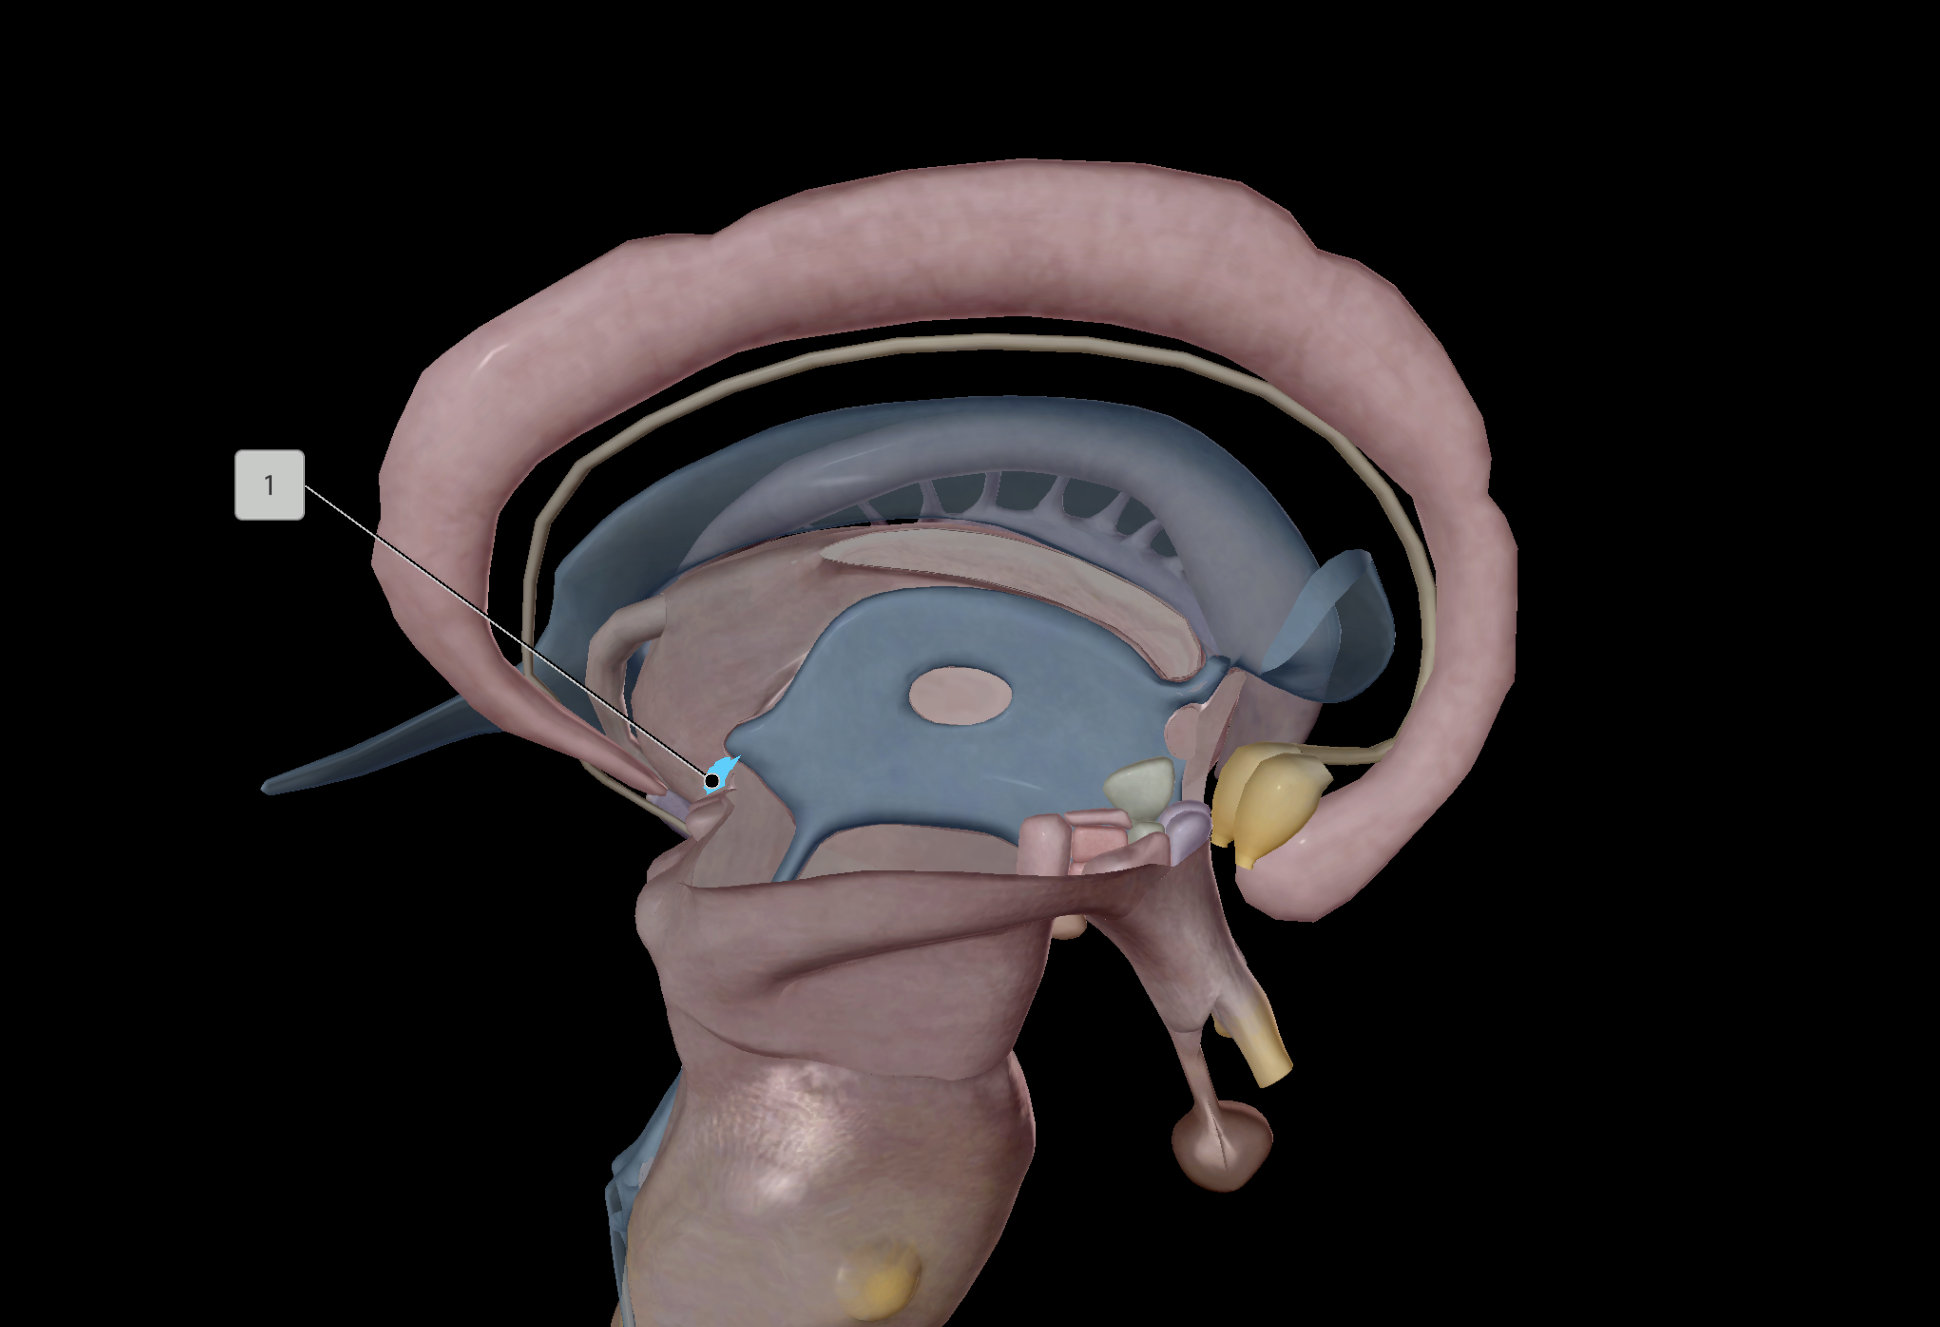

Hypothalamus

Anterior Pituitary Gland

Posterior Pituitary Gland

Pineal Gland